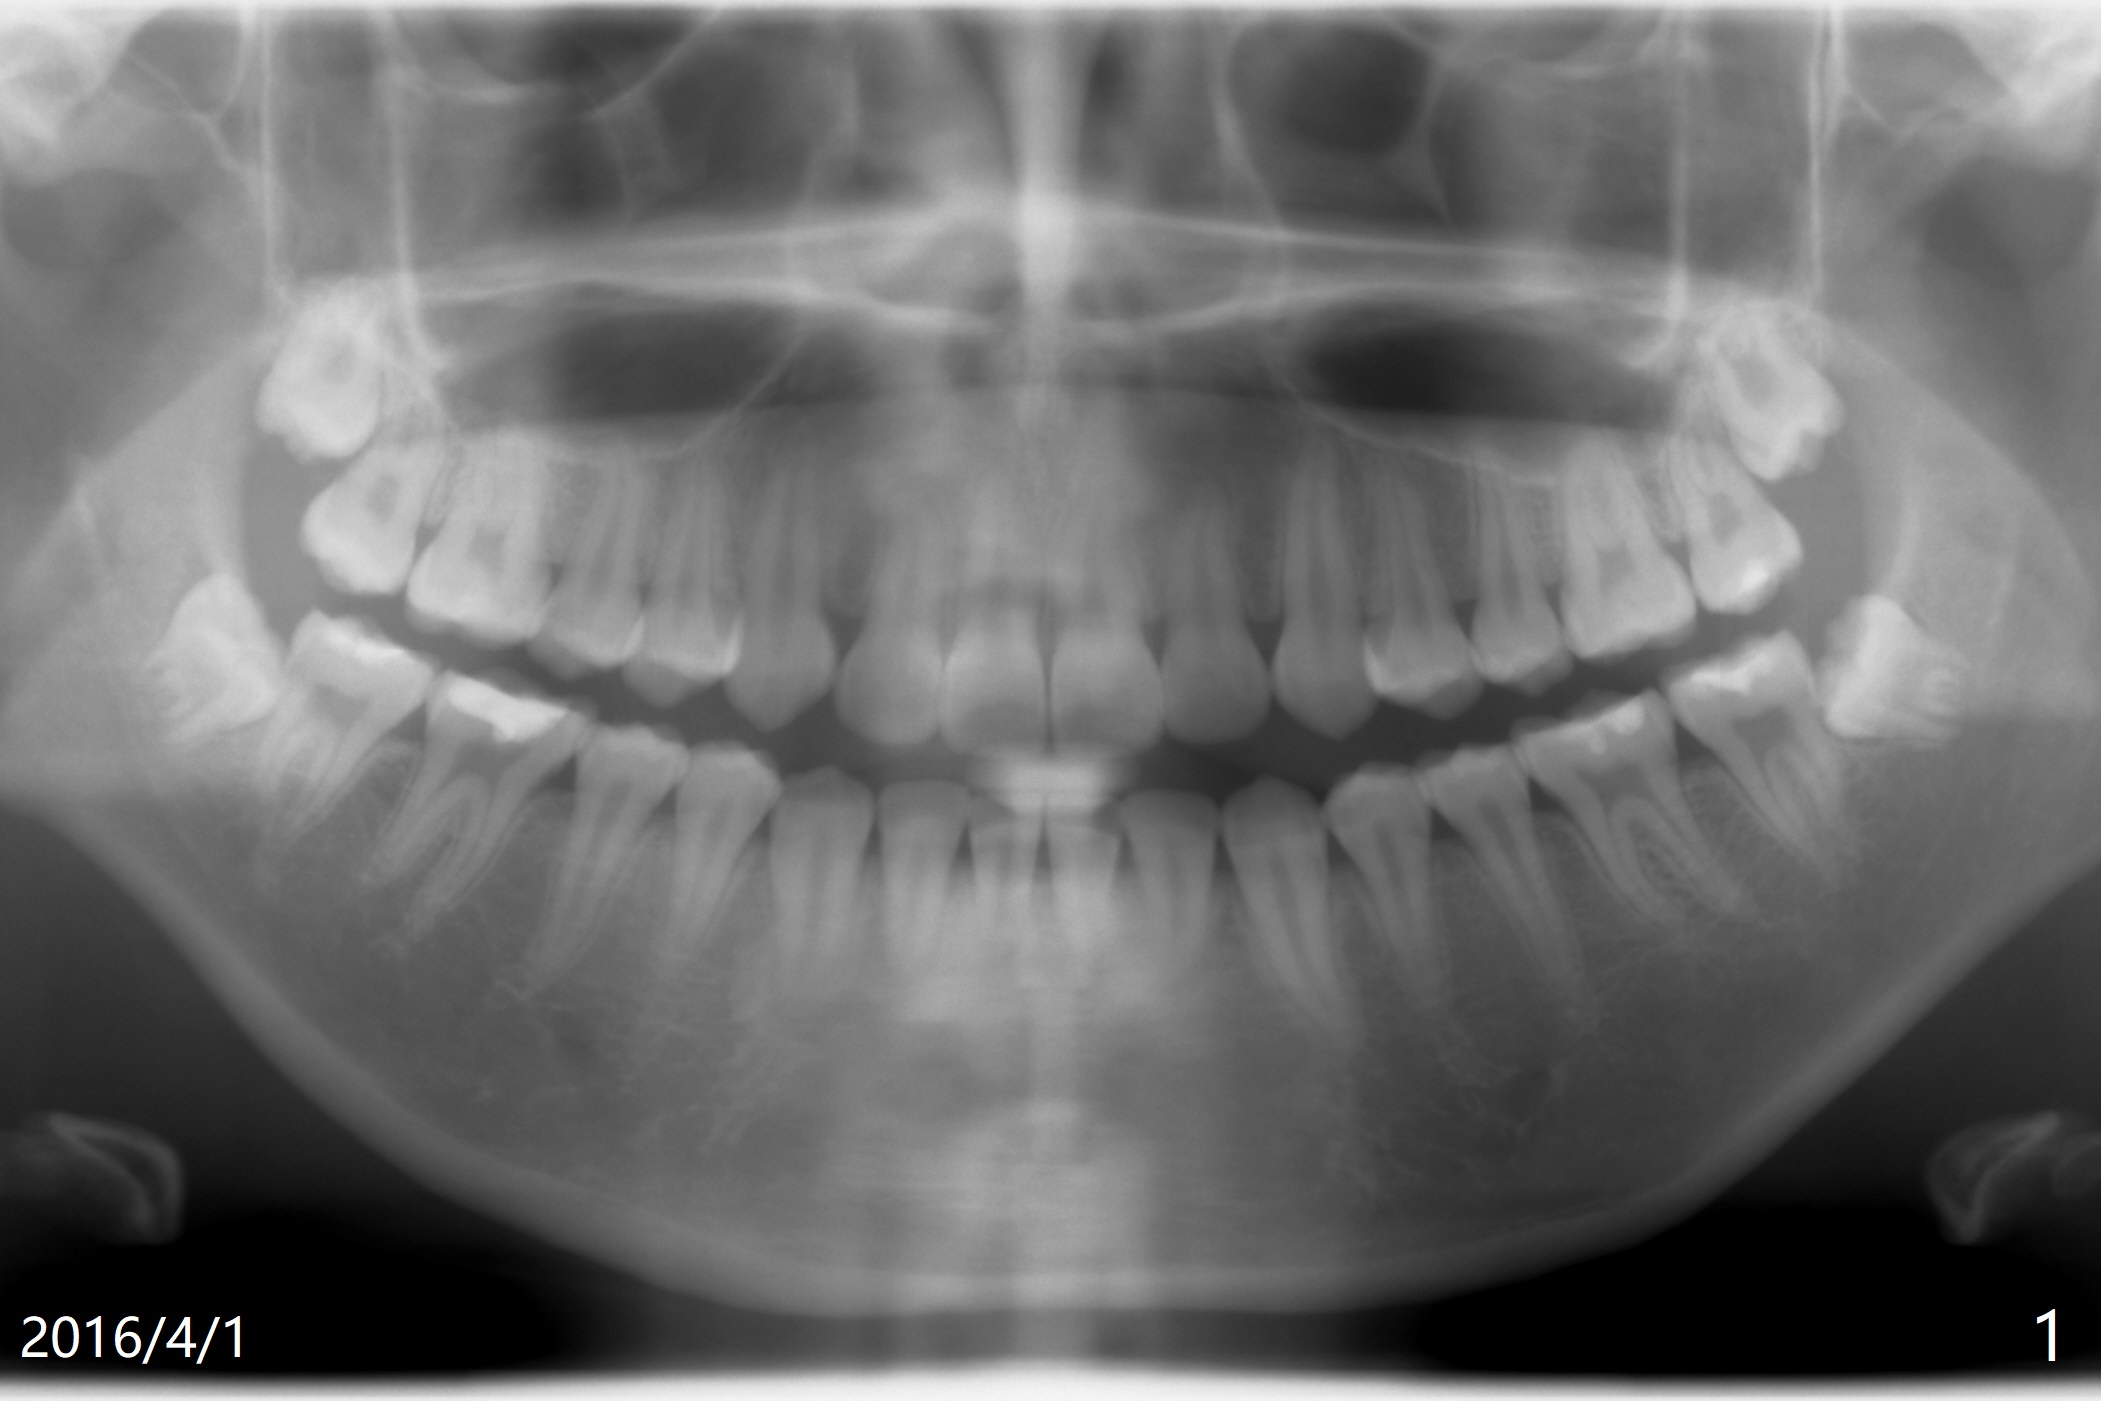

A 19-year-old woman requests extraction of #1,16,17 and 32 (Fig.1). The surgery is smooth except the fact that a surgical fissure bur tip is found to have been fractured without trace at #17. Before placement of Osteogen plug (Fig.2 O) and suture at #17, a regional panoramic X-ray for bitewing is taken. All of the sockets heal in 14 months (Fgi.3).